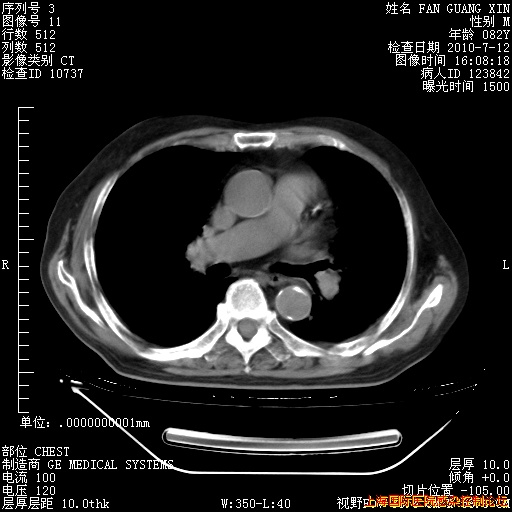

6月12日纵膈窗

海管,自昨日你和我通完话后,不知您岳父消化道症状有无缓解?体温怎样?阅读7.12日胸部ct,个人认为目前激素治疗是有效的,甲强龙减量是适宜的。因在抗痨治疗,需密切观察肝功、肾功能和血常规。不过,老年、长期住院和大量使用激素,很担心菌群失调发生